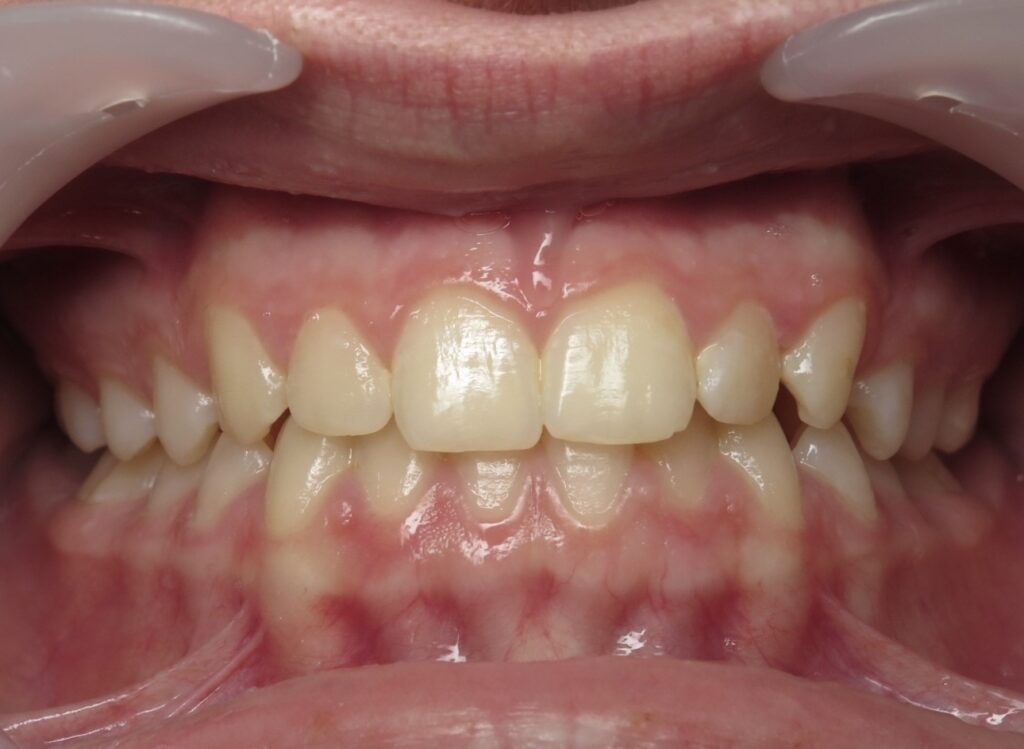

Un cas de recouvrement trop important avec bruxisme sévère :

La photo intermédiaire permet de voir que la situation en denture mixte était bien plus favorable qu’au départ. Quelle dentition aurait eu ce patient si on l’avait traité seulement à 12 ans ? et toutes les tensions dans son corps qui accompagnent ce genre de cas auraient surement perturbé sa croissance générale.

Photos à 6 ans, 9 ans et 15 ans